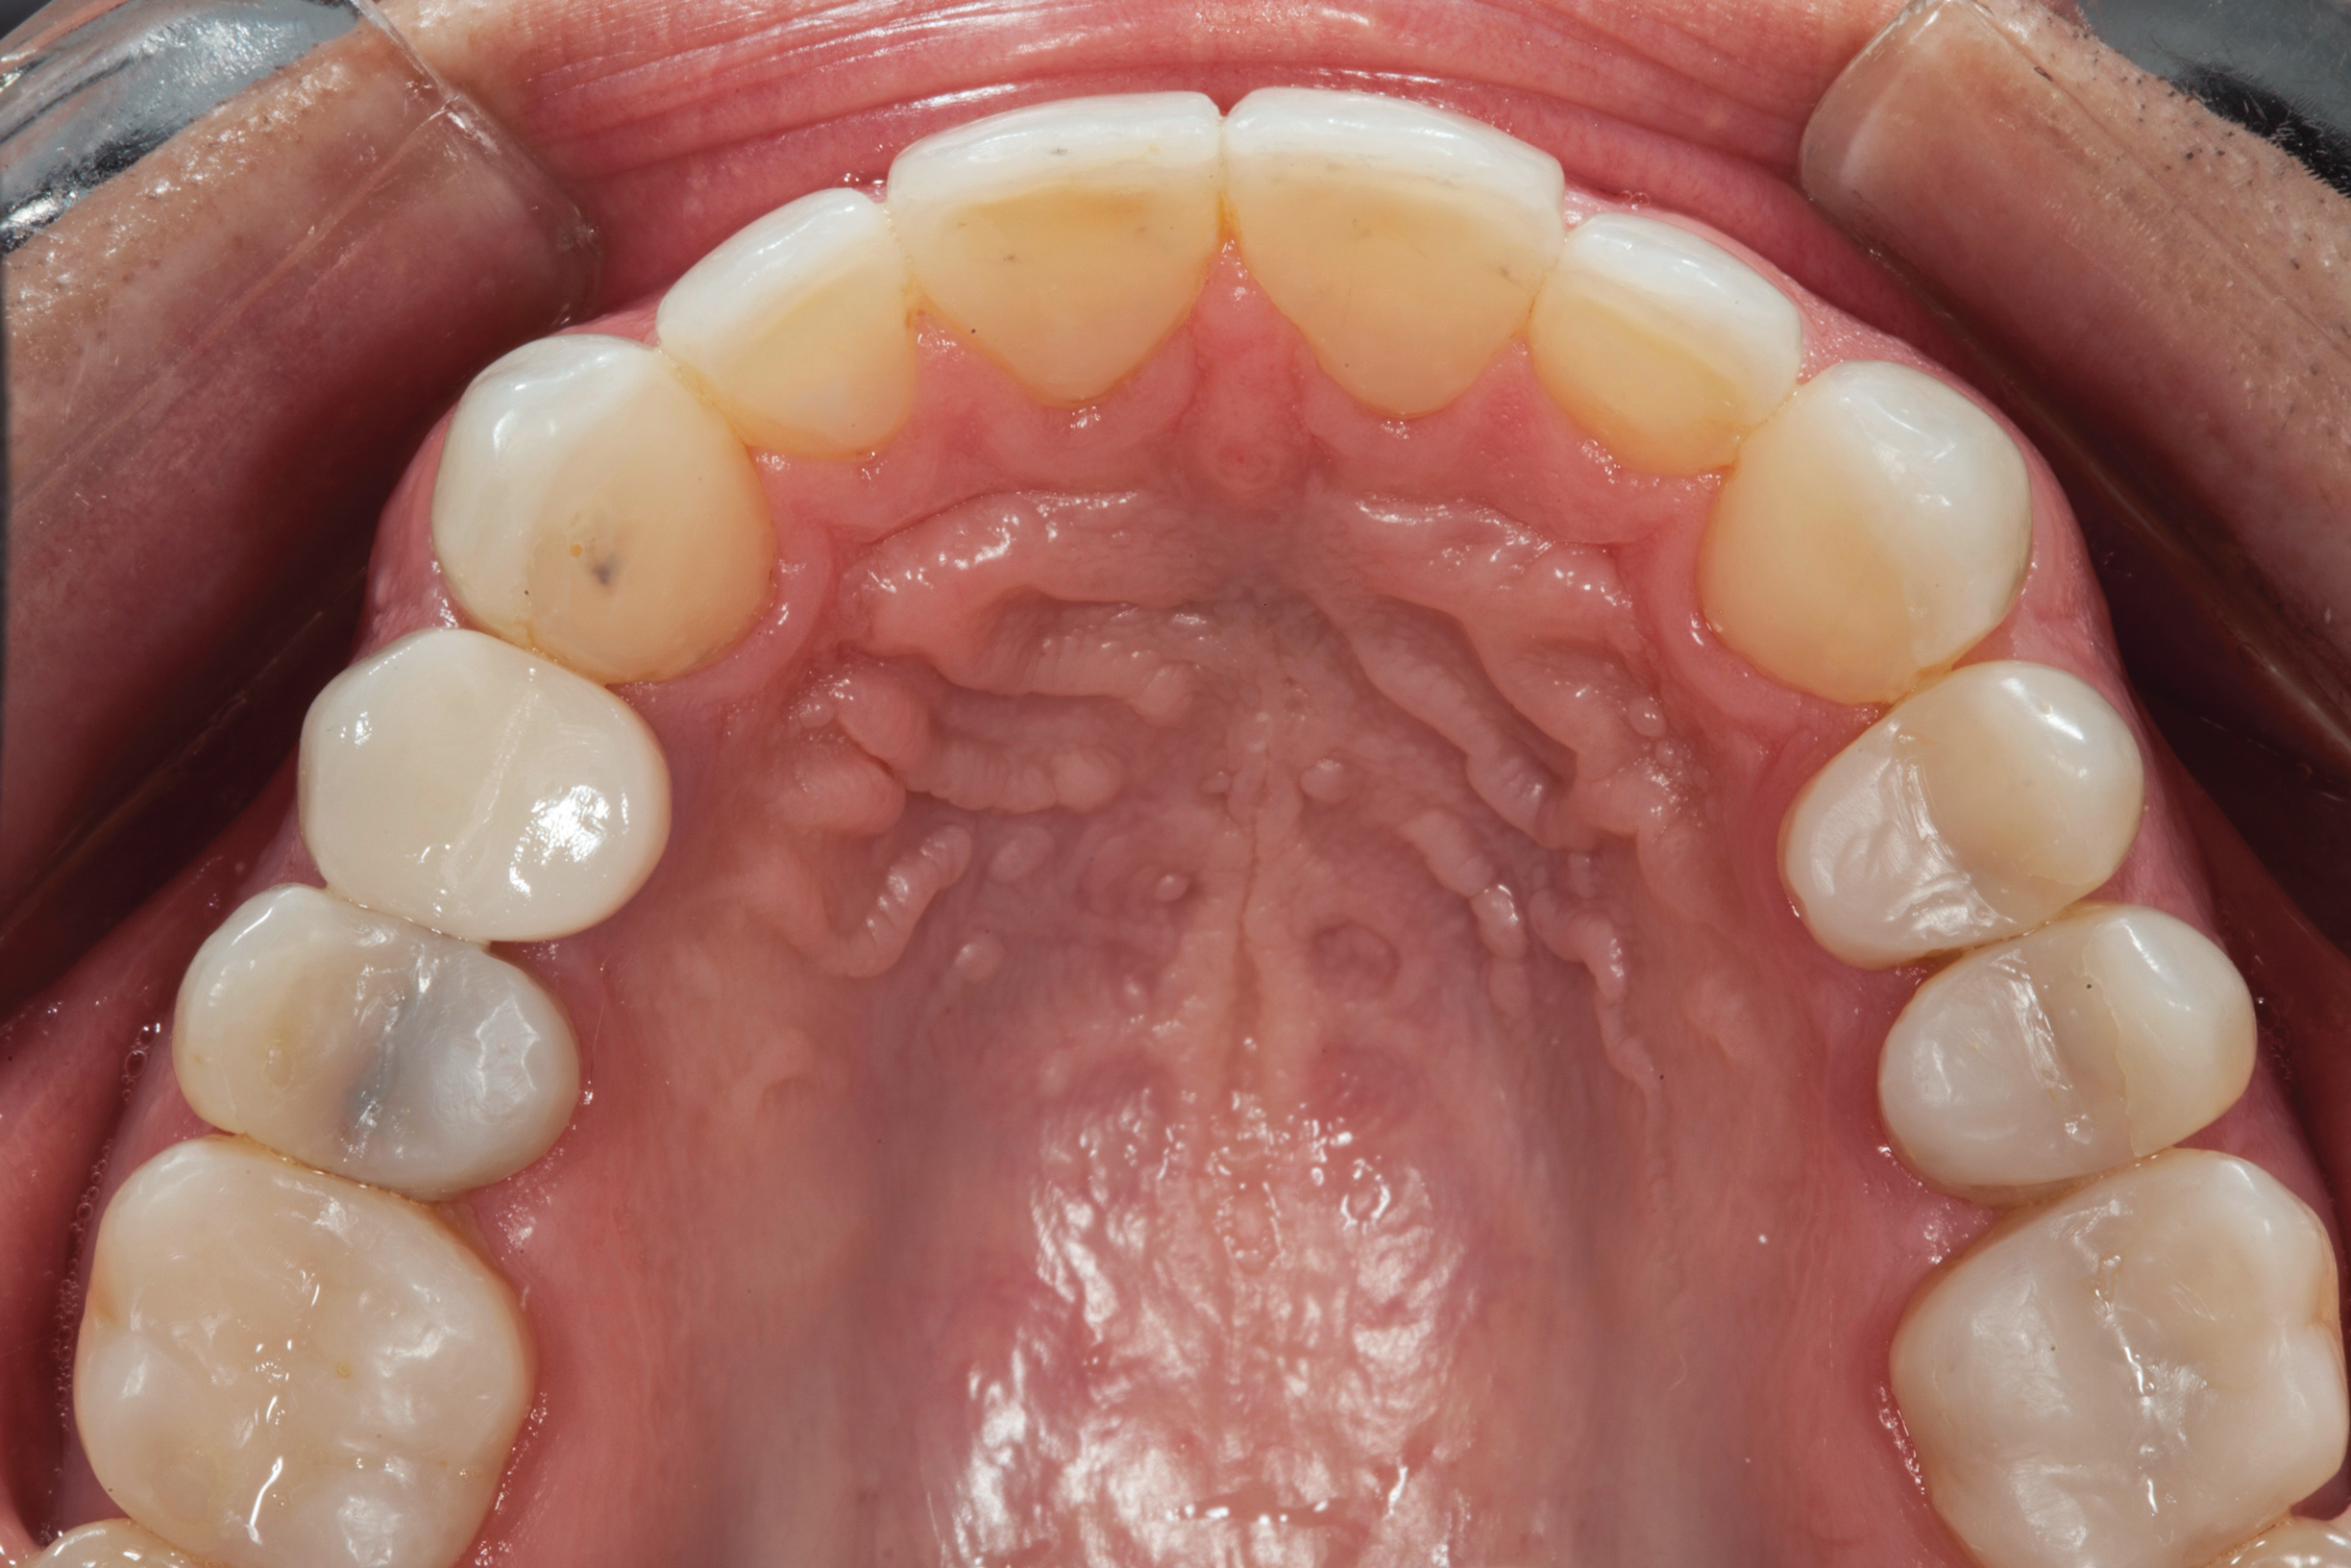

(13.) Postoperative occlusal view of upper arch.

Figure 13